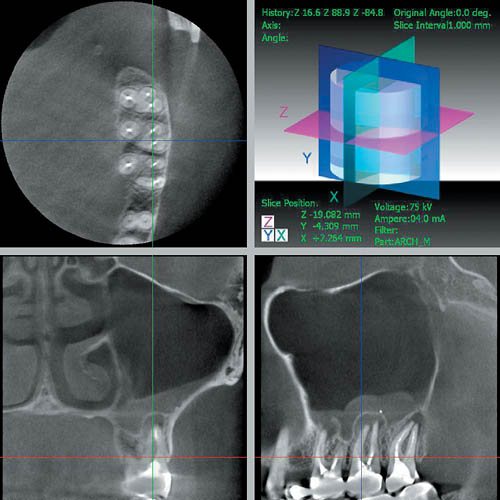

— дает возможность выявлять патологические изменения со стороны верхнечелюстных пазух, полости носа, нижнечелюстного канала (рис. 7);